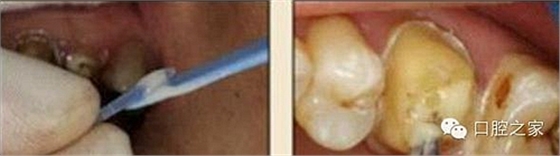

大多數(shù)醫(yī)生在樁道預(yù)備時習慣于干燥預(yù)備根管(圖 1),這樣很容易破壞根管壁的牙本質(zhì)結(jié)構(gòu),同時也可形成較厚的玷污層,影響樹脂水門汀與牙體組織的粘接。因此,臨床操作時應(yīng)選擇沖洗的方法冷卻預(yù)備根管(圖 2),防止牙膠及封閉劑粘連附著于根管壁形成第二玷污層(根管治療時形成的玷污層稱為第一玷污層),有利于樹脂水門汀與根管牙本質(zhì)的粘接。

圖1:干燥預(yù)備根管。

圖2:沖洗預(yù)備根管。